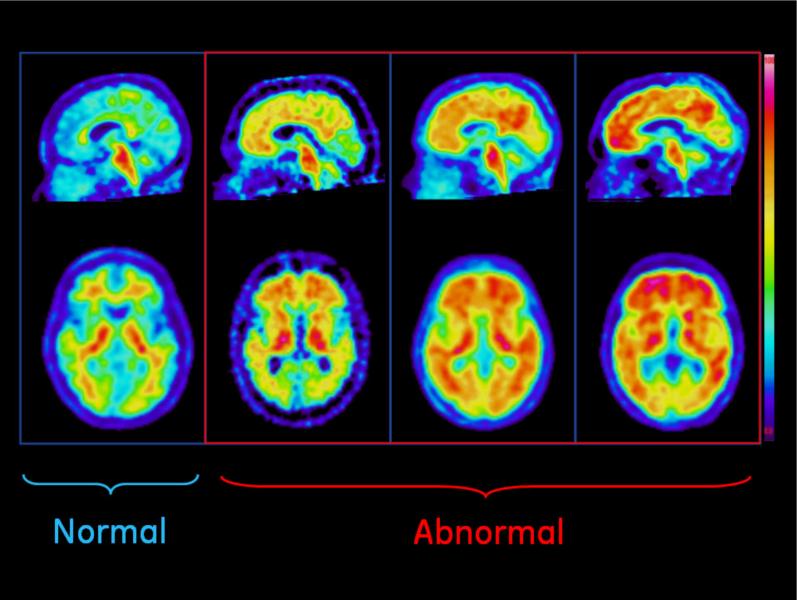

April 13, 2012 — GE Healthcare announced the preliminary results of two Phase 3 studies of its investigational positron emission tomography (PET) amyloid imaging agent, F-18 flutemetamol, where both studies met their primary endpoints.

April 11, 2012 - Siemens Healthcare is the first company worldwide to announce a complete integrated diagnostic imagingsolution proposed for the detection of amyloid plaques — one of the necessary pathological features of Alzheimer’s disease [1,2,3] — in the living brain.